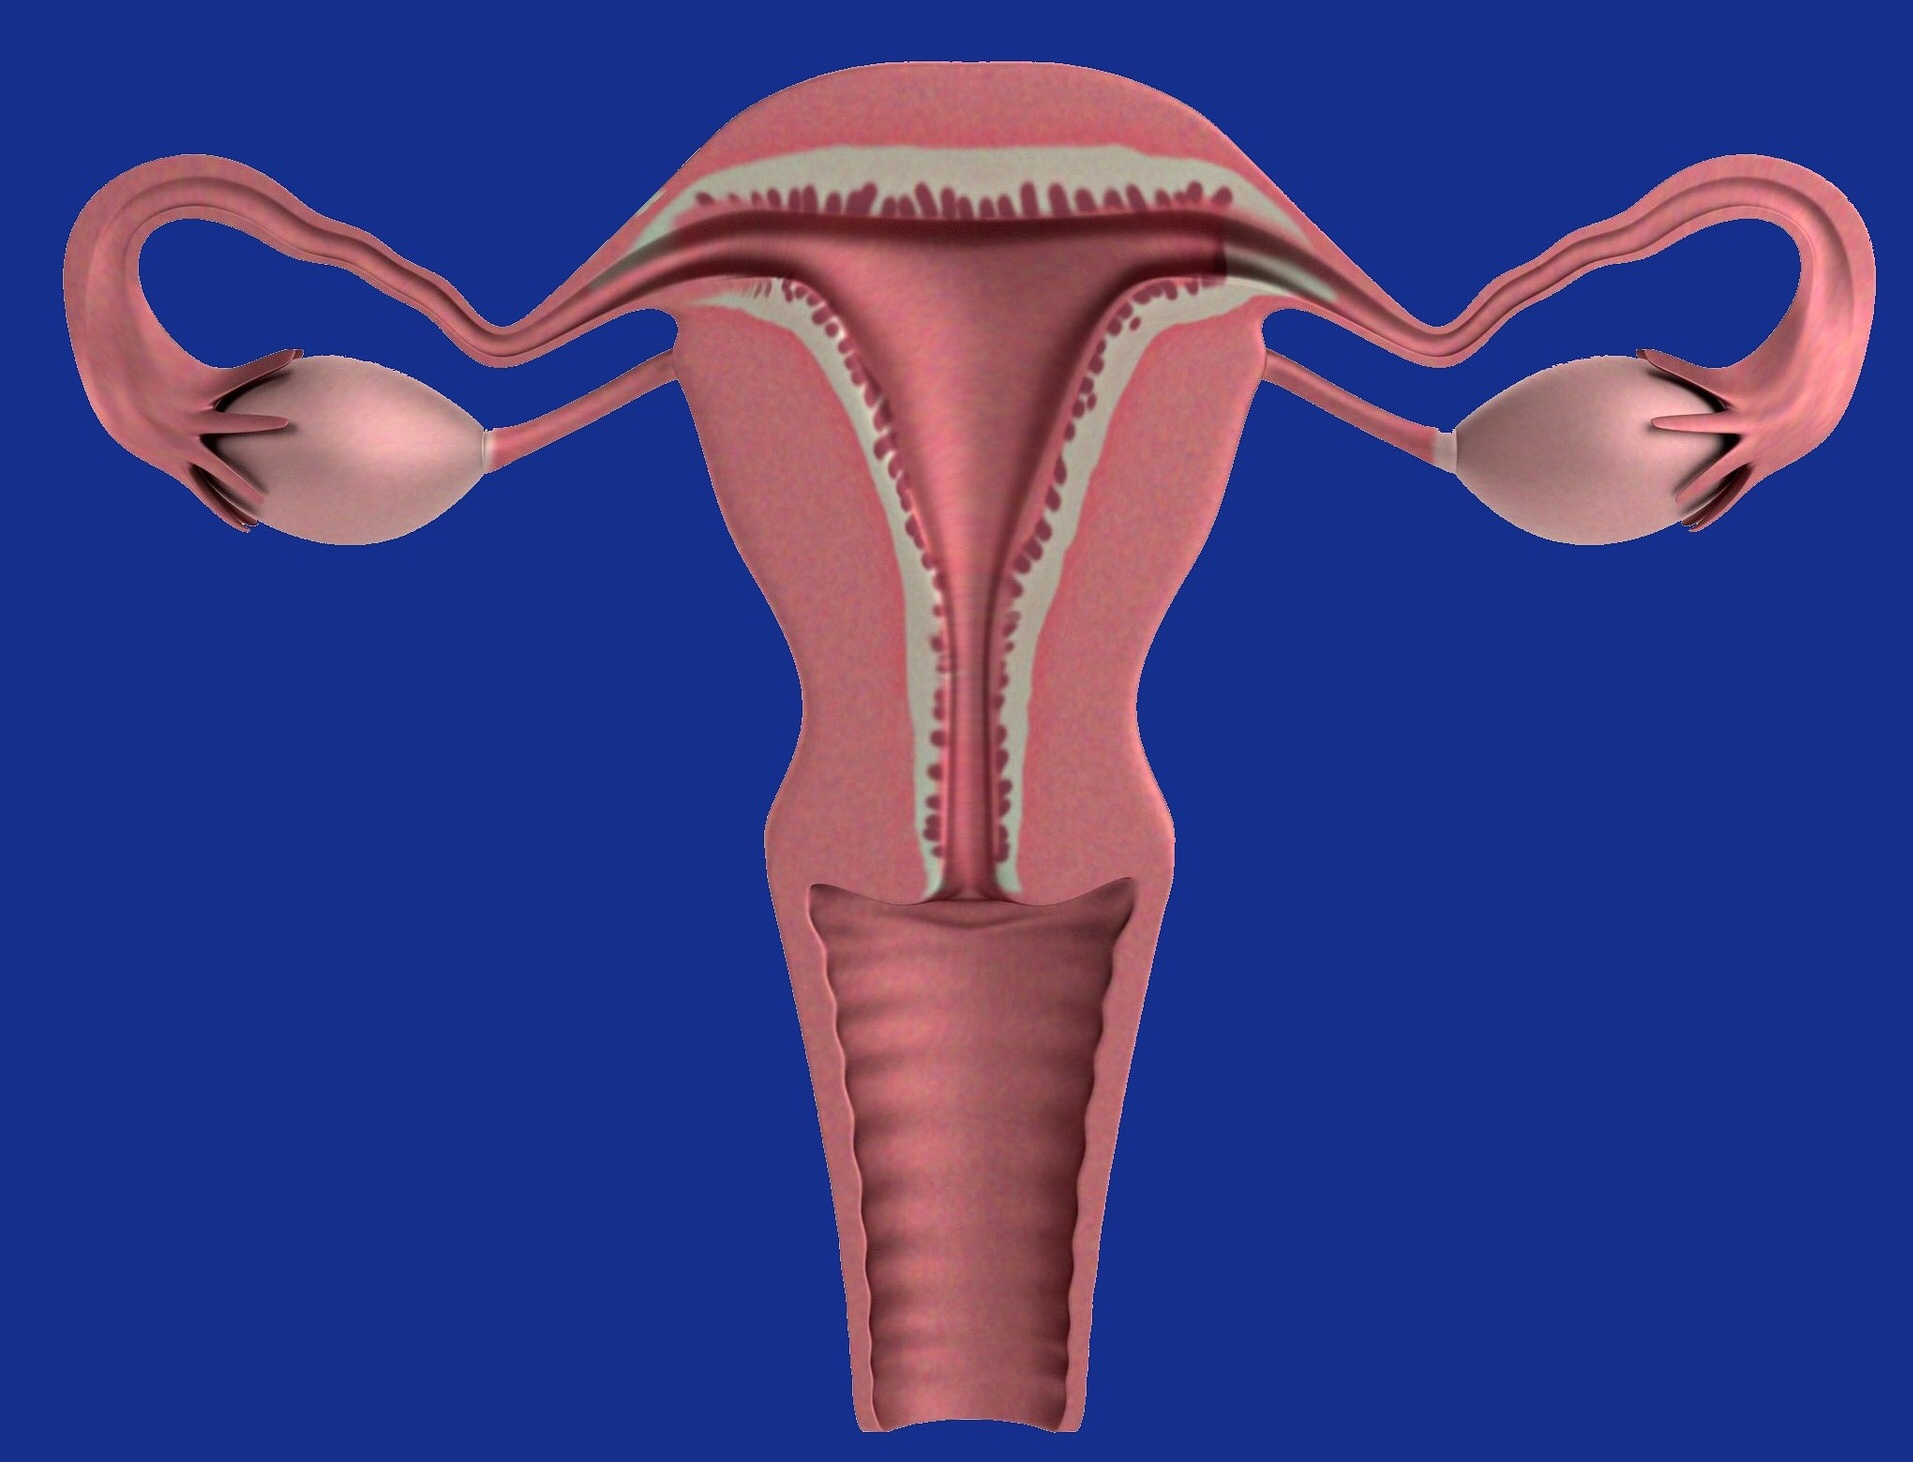

L’utero è un organo dalla forma di pera rovesciata e di natura mobile. La maggior parte delle donne nasce con un utero in posizione più o meno dritta all’interno del bacino e rivolto leggermente in avanti verso l’addome. Altre invece, presentano un utero che si inclina verso dietro, in direzione della colonna vertebrale.

L’utero è quindi retroverso perché posizionato inclinato verso il bacino, all’indietro. In casi invece meno frequenti la sua posizione va a formare un angolo aperto verso la cavità sacrale. Questo secondo caso si chiama utero retroflesso. Un utero retroverso o retroflesso potrebbe causare dolori in gravidanza. Nella maggioranza dei casi, le cause sono congenite o genetiche. Anche alcune situazioni di salute possono portare ad una conseguente retroversione dell’utero. Ne sono potenziali cause la menopausa, la gravidanza o problemi di infertilità.

Negli anni è stato dimostrato da varie ricerche mediche, che la difficoltà nel concepimento di chi soffre di utero retroverso non è molto maggiore di chi ce l’ha antiverso. Il concepimento avviene comunque se le Tube di Falloppio sono ben aperte e operative. Raccomandiamo comunque che la gravidanza sia seguita dal ginecologo che controllerà regolarmente ad ogni visita che tutto vada in modo giusto.

Generalmente verso la quattordicesima o quindicesima settimana di gravidanza, l’utero in modo naturale essendo mobile, da retroverso diventa anteroverso. Si sposta da solo in avanti e vi rimane fino alla fine della gestazione. Quindi al momento del parto l’utero sarà posizionato in modo da poter partorire correttamente e senza complicazioni.

Alcuni pensano che l’utero retroverso torni alla sua normale posizione da solo dopo la gravidanza diventando anteroverso. In realtà nella maggioranza dei casi questo non succede affatto. Infatti, circa sei settimane dopo il parto, una volta tornato in sede, l’utero retroverso torna alle sue dimensioni naturali e riprende la sua posizione originale nella pelvi.

Quindi l’utero retroverso non si aggiusta perchè non è un difetto fisico ma solo una conformazione della persona. Dopo un mese circa dal parto, quando riprende le sue dimensioni normali, l’utero ritorna ad essere come era prima, cioè retroverso. Questo perché i legamenti lo riportano al suo posto originario.

Cambiamenti di utero anteroverso potrebbero sussistere dopo la gravidanza. Il parto, infatti, potrebbe causare la retroflessione dell’utero. Anche se questa situazione avviene raramente, può accadere che i legamenti che tengono l’utero in posizione perdono la loro tensione durante la gravidanza.

Infatti, durante la gravidanza l’utero si ingrossa e i legamenti che servono per tenere l’utero in posizione tendono indebolirsi. Di conseguenza, molte donne hanno scoperto dopo una visita ginecologica post parto che purtroppo il loro utero era diventa retroflesso.